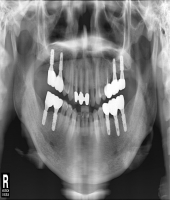

| ● 진료과목 : [임플란트] 충치 및 치주질환 임플란트

| ● 내용 : 충치와 치주질환에 의한 치아상실로 임플란트 치료함. |